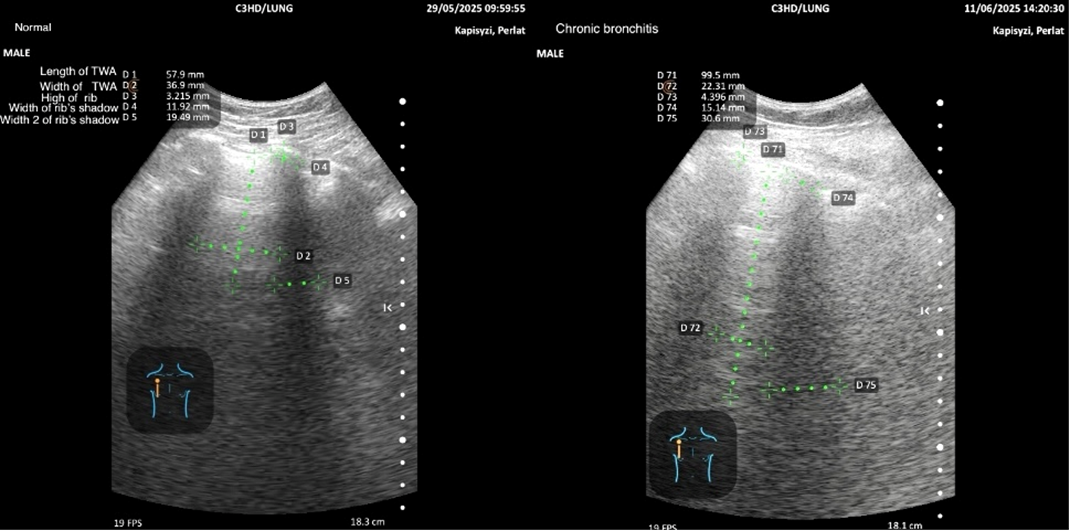

The overall project is structured in three complementary parts: (1) echographic features of emphysema compared with normal subjects, (2) chronic bronchitis compared with normal subjects (the focus of the present manuscript), and (3) emphysema versus chronic bronchitis. Representative examples of measurements by region, together with pictograms, are presented to illustrate the methodology.

The methodology for quantifying regional variables in normal subjects and bronchitis patients is illustrated with pictograms and representative examples